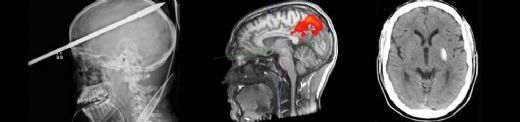

Düşme, özellikle yaşlı bireylerde ve çocuklarda yaygın bir yaralanma sebebidir. Bu tür yaralanmalar sonucunda beyin kanaması gibi ciddi durumlar gelişebilir. Beyin kanaması, kafaya alınan bir darbe sonucunda beyin dokusunun içinde veya çevresinde kan birikmesi durumudur. Bu makalede, düşme sonucunda meydana gelebilecek beyin kanamasının belirtileri ve tedavi yöntemleri detaylı bir şekilde incelenecektir. Beyin Kanaması Nedir?Beyin kanaması, kafatası içindeki kan damarlarının yırtılması ya da sızdırması sonucu meydana gelir. İki ana türü vardır:

Bu tür kanamalar, beyin hücrelerine zarar verebilir ve hayatı tehdit eden durumlar oluşturabilir. Düşme Sonrası Beyin Kanaması BelirtileriDüşme sonucu oluşan beyin kanamasının belirtileri, kanamanın türüne, büyüklüğüne ve yerine bağlı olarak değişiklik gösterebilir. Genel olarak gözlemlenen belirtiler şunlardır:

Bu belirtiler hemen ortaya çıkmayabilir; bazen düşmeden saatler veya günler sonra gelişebilir. Bu nedenle, düşme sonrası belirtilerin dikkatle izlenmesi önemlidir. Tedavi YöntemleriDüşme sonrası beyin kanaması tedavisi, kanamanın boyutuna ve yerine bağlı olarak değişiklik gösterir. Tedavi yöntemleri şunlardır: